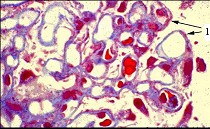

- 单项选择题图-1可见上皮下少量嗜复红蛋白沉积(1)(Masson),图-2可见上皮下少量电子致密物沉积沉积(D), 上皮细胞足突融合,其病理可诊断为 ( )

A、Ⅰ期膜性肾病